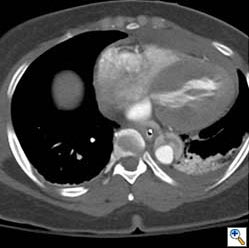

Acute Nontraumatic Thoracic Aortic Dissection

Clinical Policy: Critical Issues in the Evaluation and Management of Adult Patients With Suspected Acute Nontraumatic Thoracic Aortic Dissection ... Document Retrieval